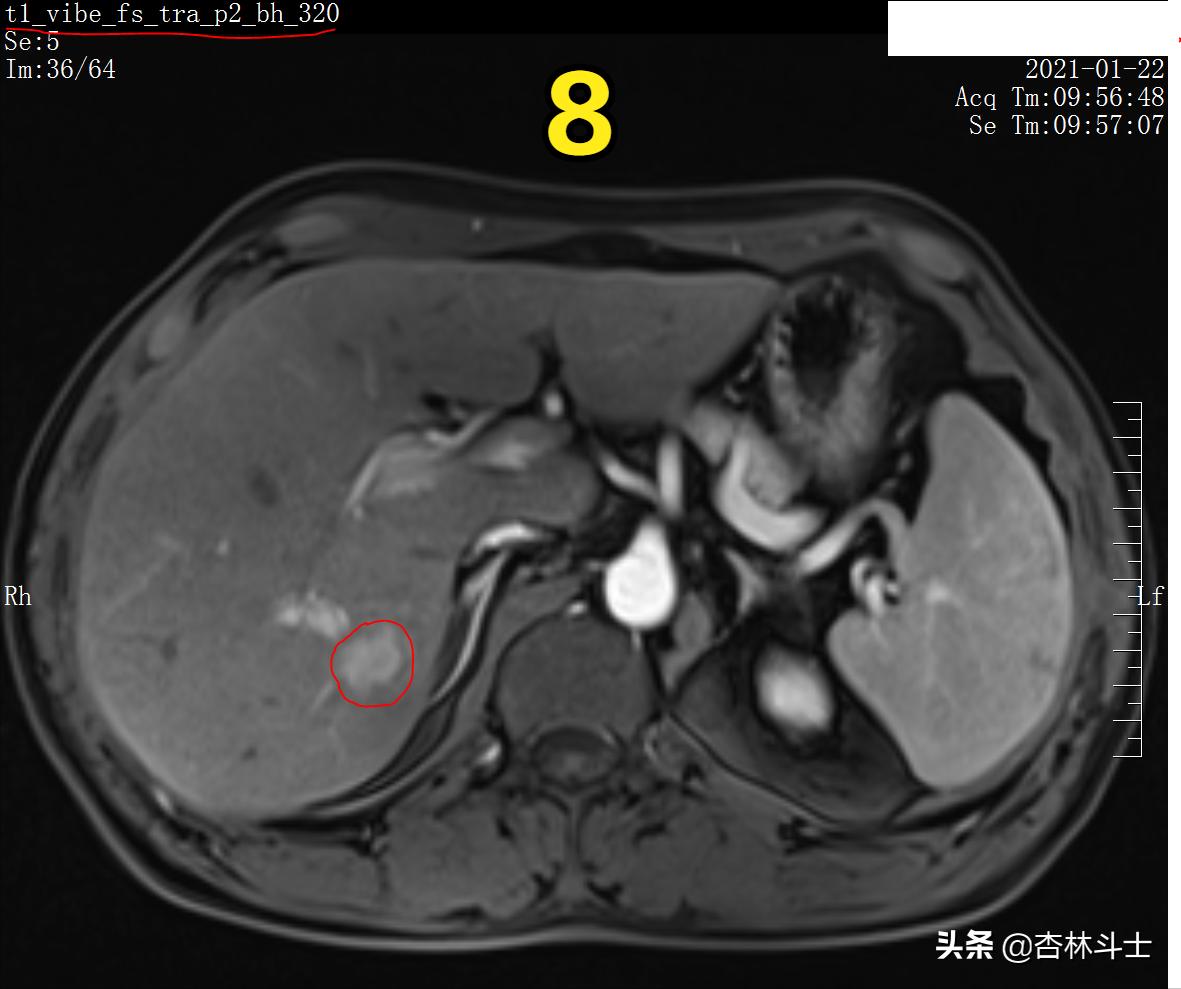

图8 T1压脂动脉期

图9 T1压脂动脉期

图8、9为T1压脂动脉期,可见病灶呈不均匀明显强化。